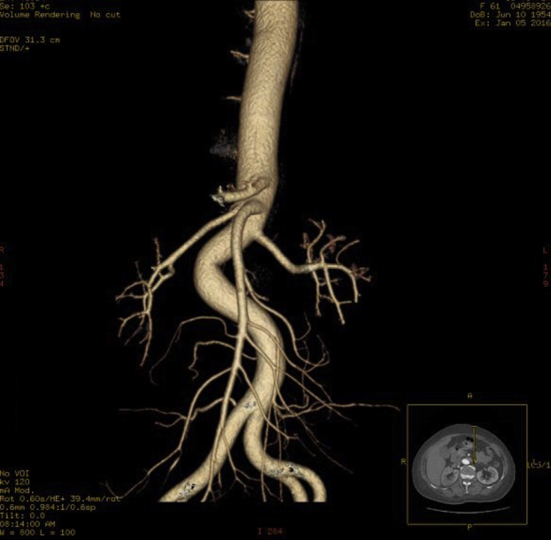

Figure 5.

Abdominal three dimensional reconstruction of the superior mesenteric artery and its branches indicated blood flow patency.